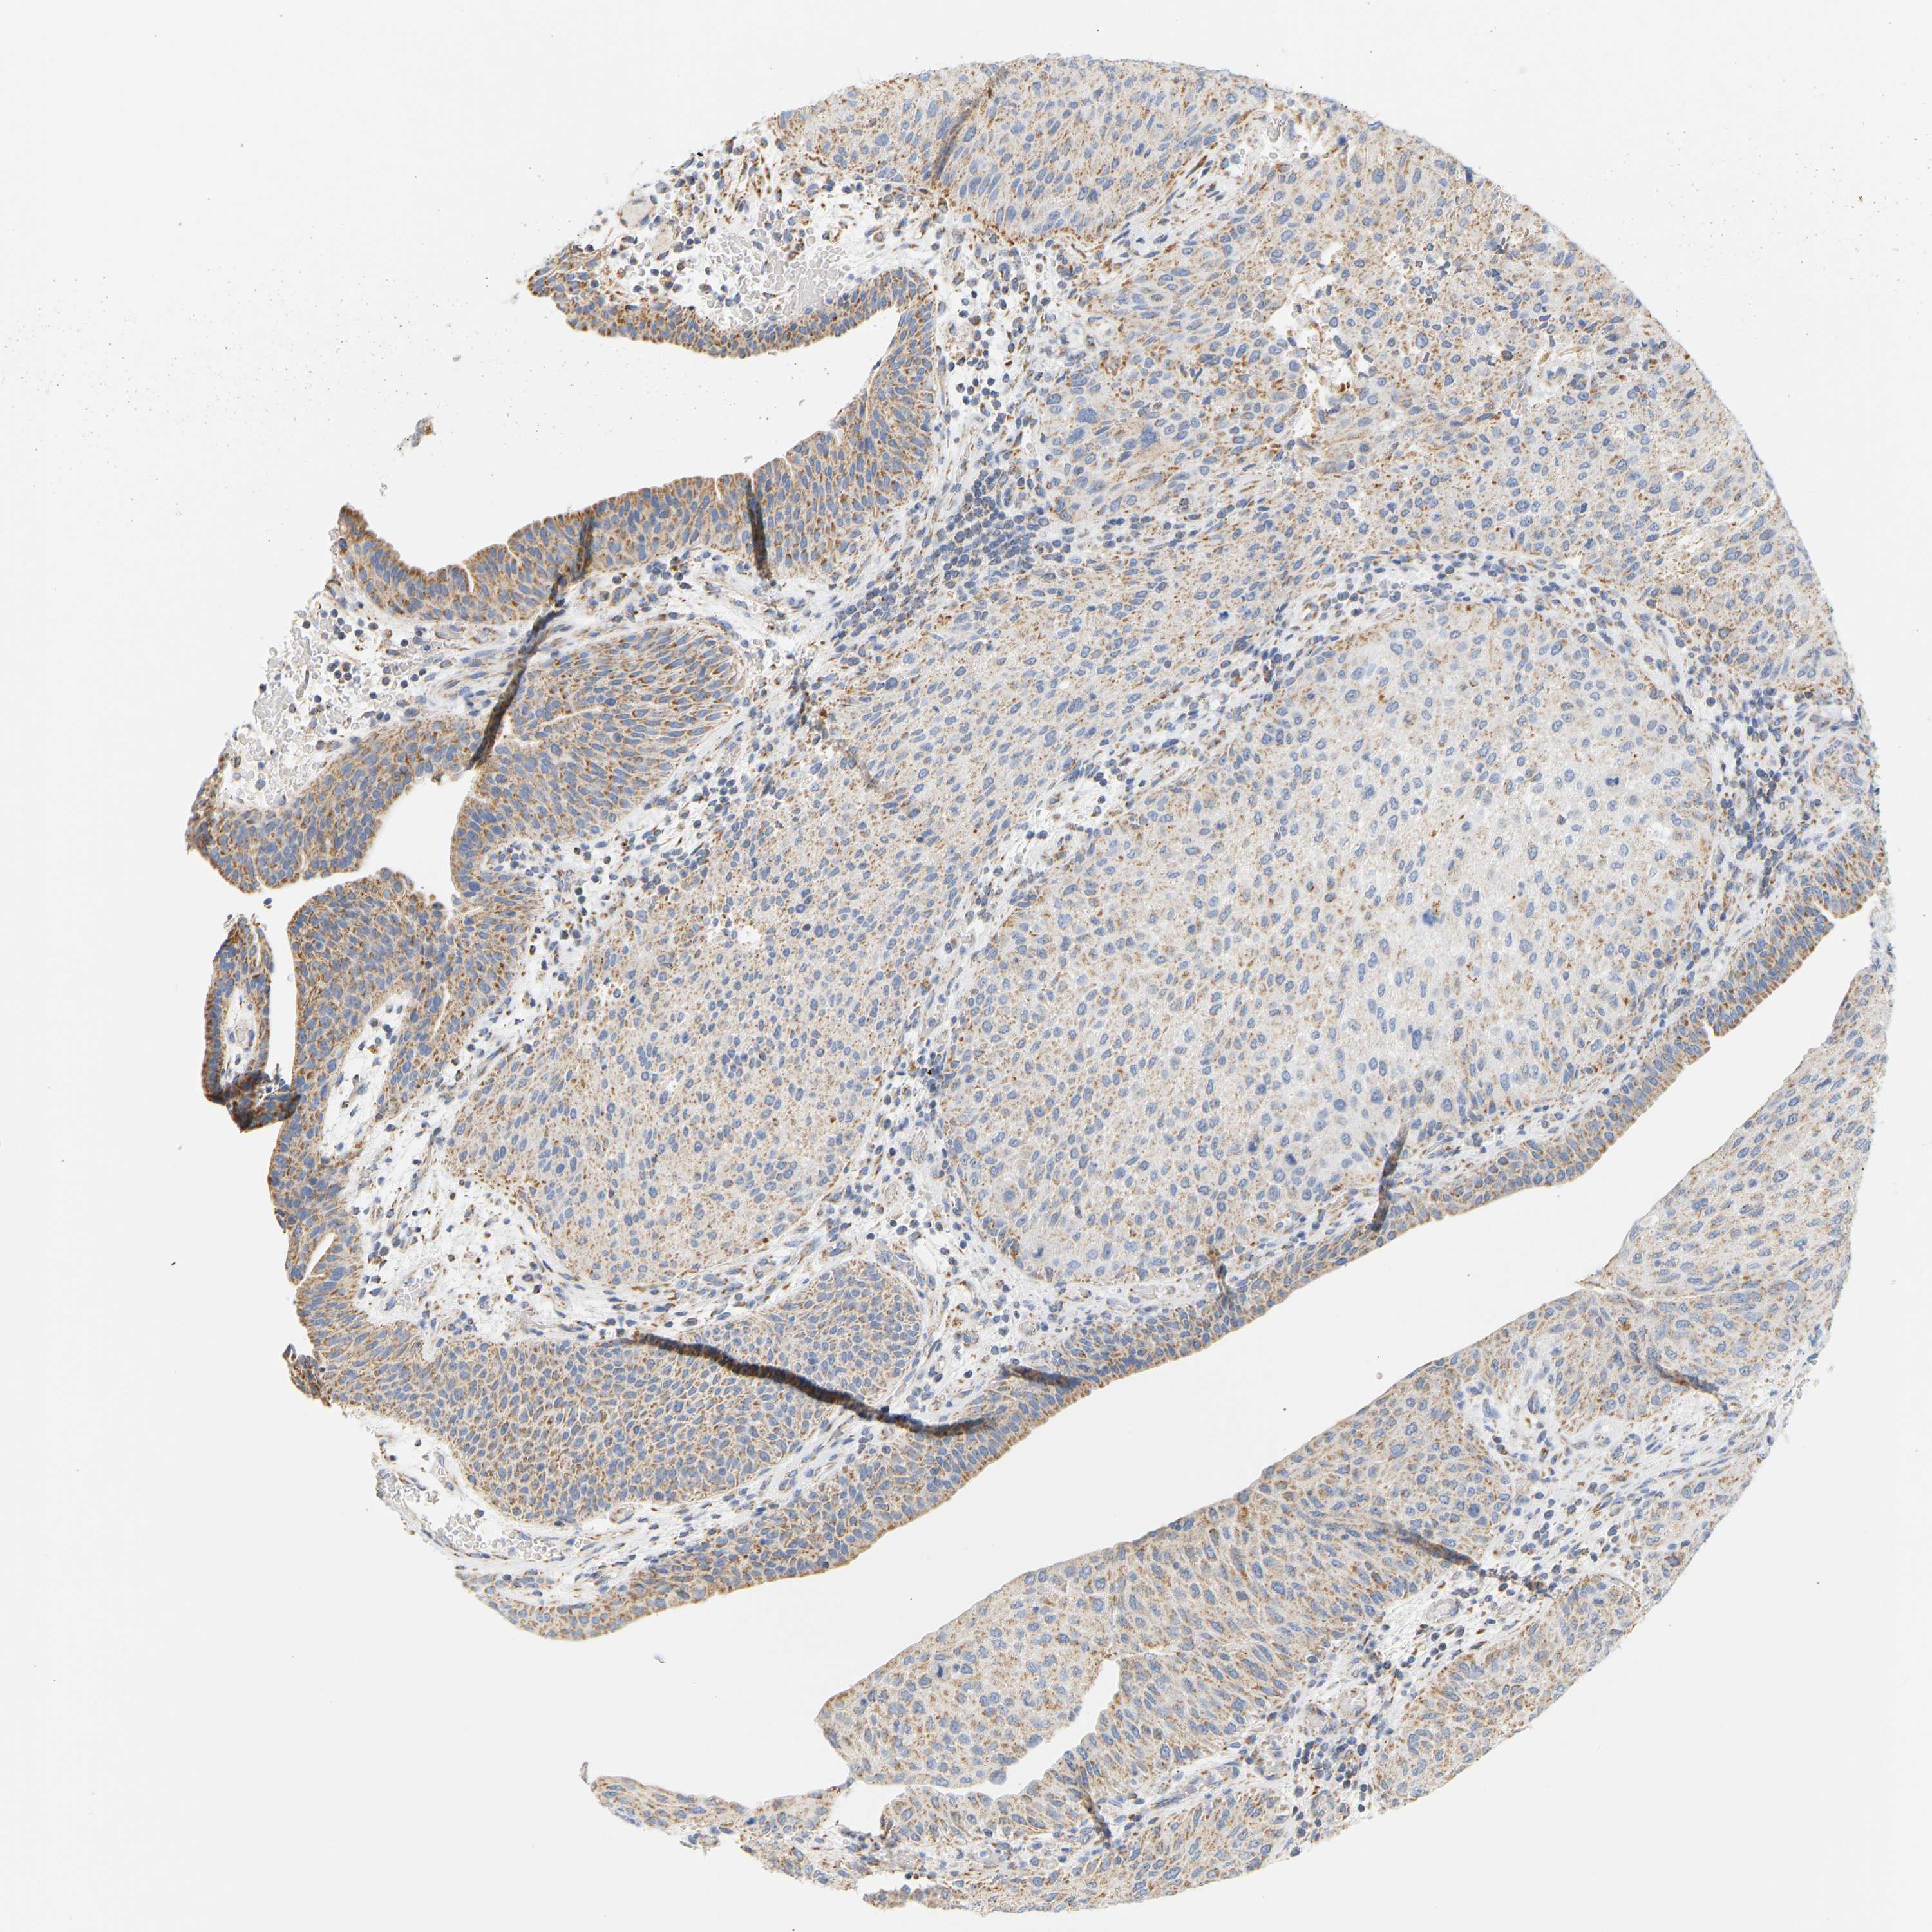

UROTHELIAL CANCER - Protein expressioni

A mouse-over function shows sample information and annotation data. Click on an image to view it in a full screen mode. Samples can be filtered based on level of antibody staining by selecting one or several of the following categories: high, medium, low and not detected. The assay and annotation is described here.

Note that samples used for immunohistochemistry by the Human Protein Atlas do not correspond to samples in the TCGA dataset.

Antibody stainingi

Antibody staining in the annotated cell types in the current human tissue is reported as not detected, low, medium, or high, based on conventional immunohistochemistry profiling in selected tissues. This score is based on the combination of the staining intensity and fraction of stained cells.

Each image is clickable and will lead to virtual microscopy that enables deeper exploration of all samples and also displays staining intensity scores, fraction scores and subcellular localization as well as patient and tissue information for each sample.

Antibody HPA018173

Antibody HPA023211

Staining

High

Medium

Low

Not detected

Intensity

Strong

Moderate

Weak

Negative

Quantity

>75%

75%-25%

<25%

None

Location

Nuclear

Cytoplasmic/membranous

Cytoplasmic/membranous,nuclear

Urothelial carcinoma, Low grade

Urothelial carcinoma, High grade